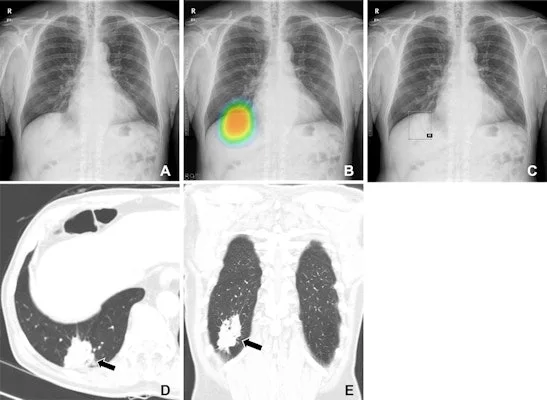

(2) Imaging Tests (영상 검사)

X-ray (엑스레이) Basic screening to check for masses. (기본적인 검사로 종양 여부 확인.)

CT Scan (컴퓨터 단층촬영, CT) Provides detailed images of the tumor’s size and location. (종양 크기와 위치를 정밀하게 확인.)

MRI (자기공명영상, MRI) Useful for soft tissue evaluation. (연부 조직(근육, 신경 등) 평가에 유용.)

PET-CT (양전자 방출 단층촬영, PET-CT) Detects metabolically active cancer cells. (대사 활동이 활발한 암세포를 찾음.)